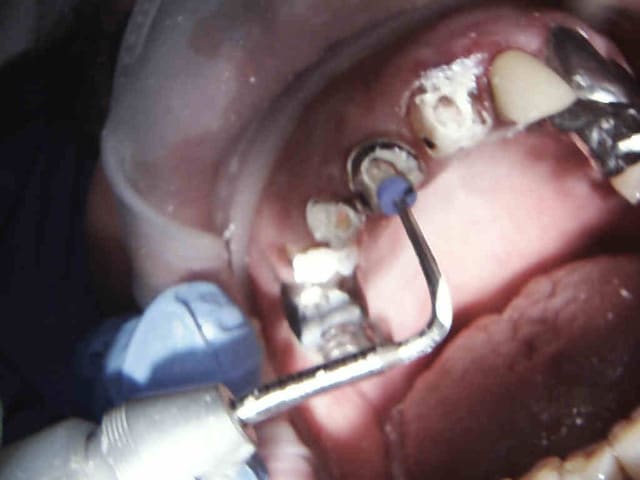

Et 2 autres pour terminer la journée. Ca fait 5 endos molaires aujourd'hui.

Pas trouvé de MV2 sur la 7.